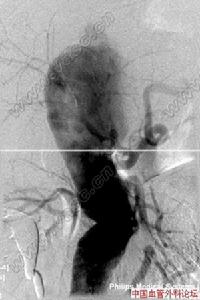

主動脈竇動脈瘤破裂7.逆行升主動脈造影可確診,表現為動脈竇擴大畸形,右心室流出道和肺動脈或右心房有造影劑顯影。

主動脈竇動脈瘤破裂主動脈竇動脈瘤是一種罕見的先天畸形,約占先天性心臟病患病率的2%~3.56%,其破入右室者最多,其次為右房。發生原因主要是胚胎期竇壁中層彈力纖維發育不良,在主動脈內高壓影響下,該薄弱處逐漸變薄擴張,呈囊袋狀突出,當壓力突然增加時破裂,由於主動脈和破入心腔間存在著較大的壓力階差,可產生大量的左向右分流,因而導致全心容量負荷增加,特別是外破口較大或破入右房者,病情進展快,容易發生充血性心力衰竭,部分患者易繼發心內膜炎、心律紊亂、腎功能衰竭等嚴重併發症。臨床多表現為起病急、進展快。一般認為,主動脈竇動脈瘤破裂之前多無明顯症狀和體徵,一旦破裂,即產生劇烈胸痛及顯著的血流動力學改變。破入右室、右房者可出現右心衰竭,呈進行性加重。體徵有胸骨左緣第3、4肋間連續性響亮機器樣雜音,常伴有肺動脈高壓、右心功能不全及脈壓差增大的表現。首次聽診往往有主動脈瓣受損的印象,易誤診為主動脈瓣關閉不全,本例即是此種情況。超聲心動圖是最佳的無創診斷法,可直接顯示主動脈竇動脈瘤的起源形態、突入的心腔位置、竇瘤破口大小、是否合併其他心臟畸形、分流的性質、時相、最大流速,提供血流動力學資料。一旦瘤體破裂,預後不良,可在數周至數月內因嚴重併發症死亡。內科治療只能起到短暫的減輕作用,手術治療往往可以獲得滿意的效果。該戰士因沒有及時手術,導致急性腎功能衰竭並時間過長,多臟器衰竭而死亡。